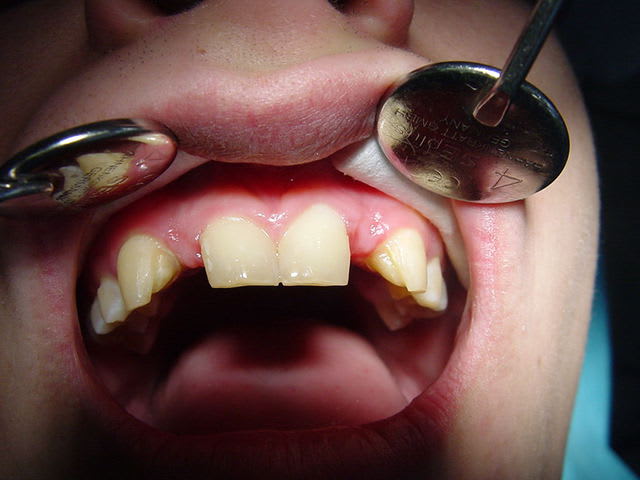

bonjour, le cas :

Dsc00091 vo4p11 - Eugenol

rebonjour, le provisoire : excuse pour la qualité des photos

(sony cybertshot première génération 2.1mp....)

préparations pour bridge collé ...des commentaires?

Dsc00088 s3ie5k - Eugenol

Dsc00092 jmfmzu - Eugenol

résultat premier bridges collés Emax

à voir dans le temps...

gestion du temps provisoire pas évident

surtout sur un étudiant présent que le WE..

et encore désolé pour l'iconographie (pas ma préoccupation majeure car un peu pris ds le rythme .. )